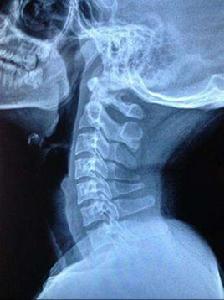

具有頭、肩、頸、臂的疼痛及相應的壓痛點,X線片上沒有椎間隙狹窄等明顯的退行性改變,但可以有頸椎生理曲線的改變,椎體間不穩定及輕度骨質增生等變化。此型在臨床上極為常見,是最早期的頸椎病。由於症狀較輕,往往重視不夠,以致反覆發作使病情加重,不少反覆落枕的病人即屬於此種改變。從大量的臨床觀察證實,此型實際上是頸椎病的最初階段,也是治療最為有利的時機。